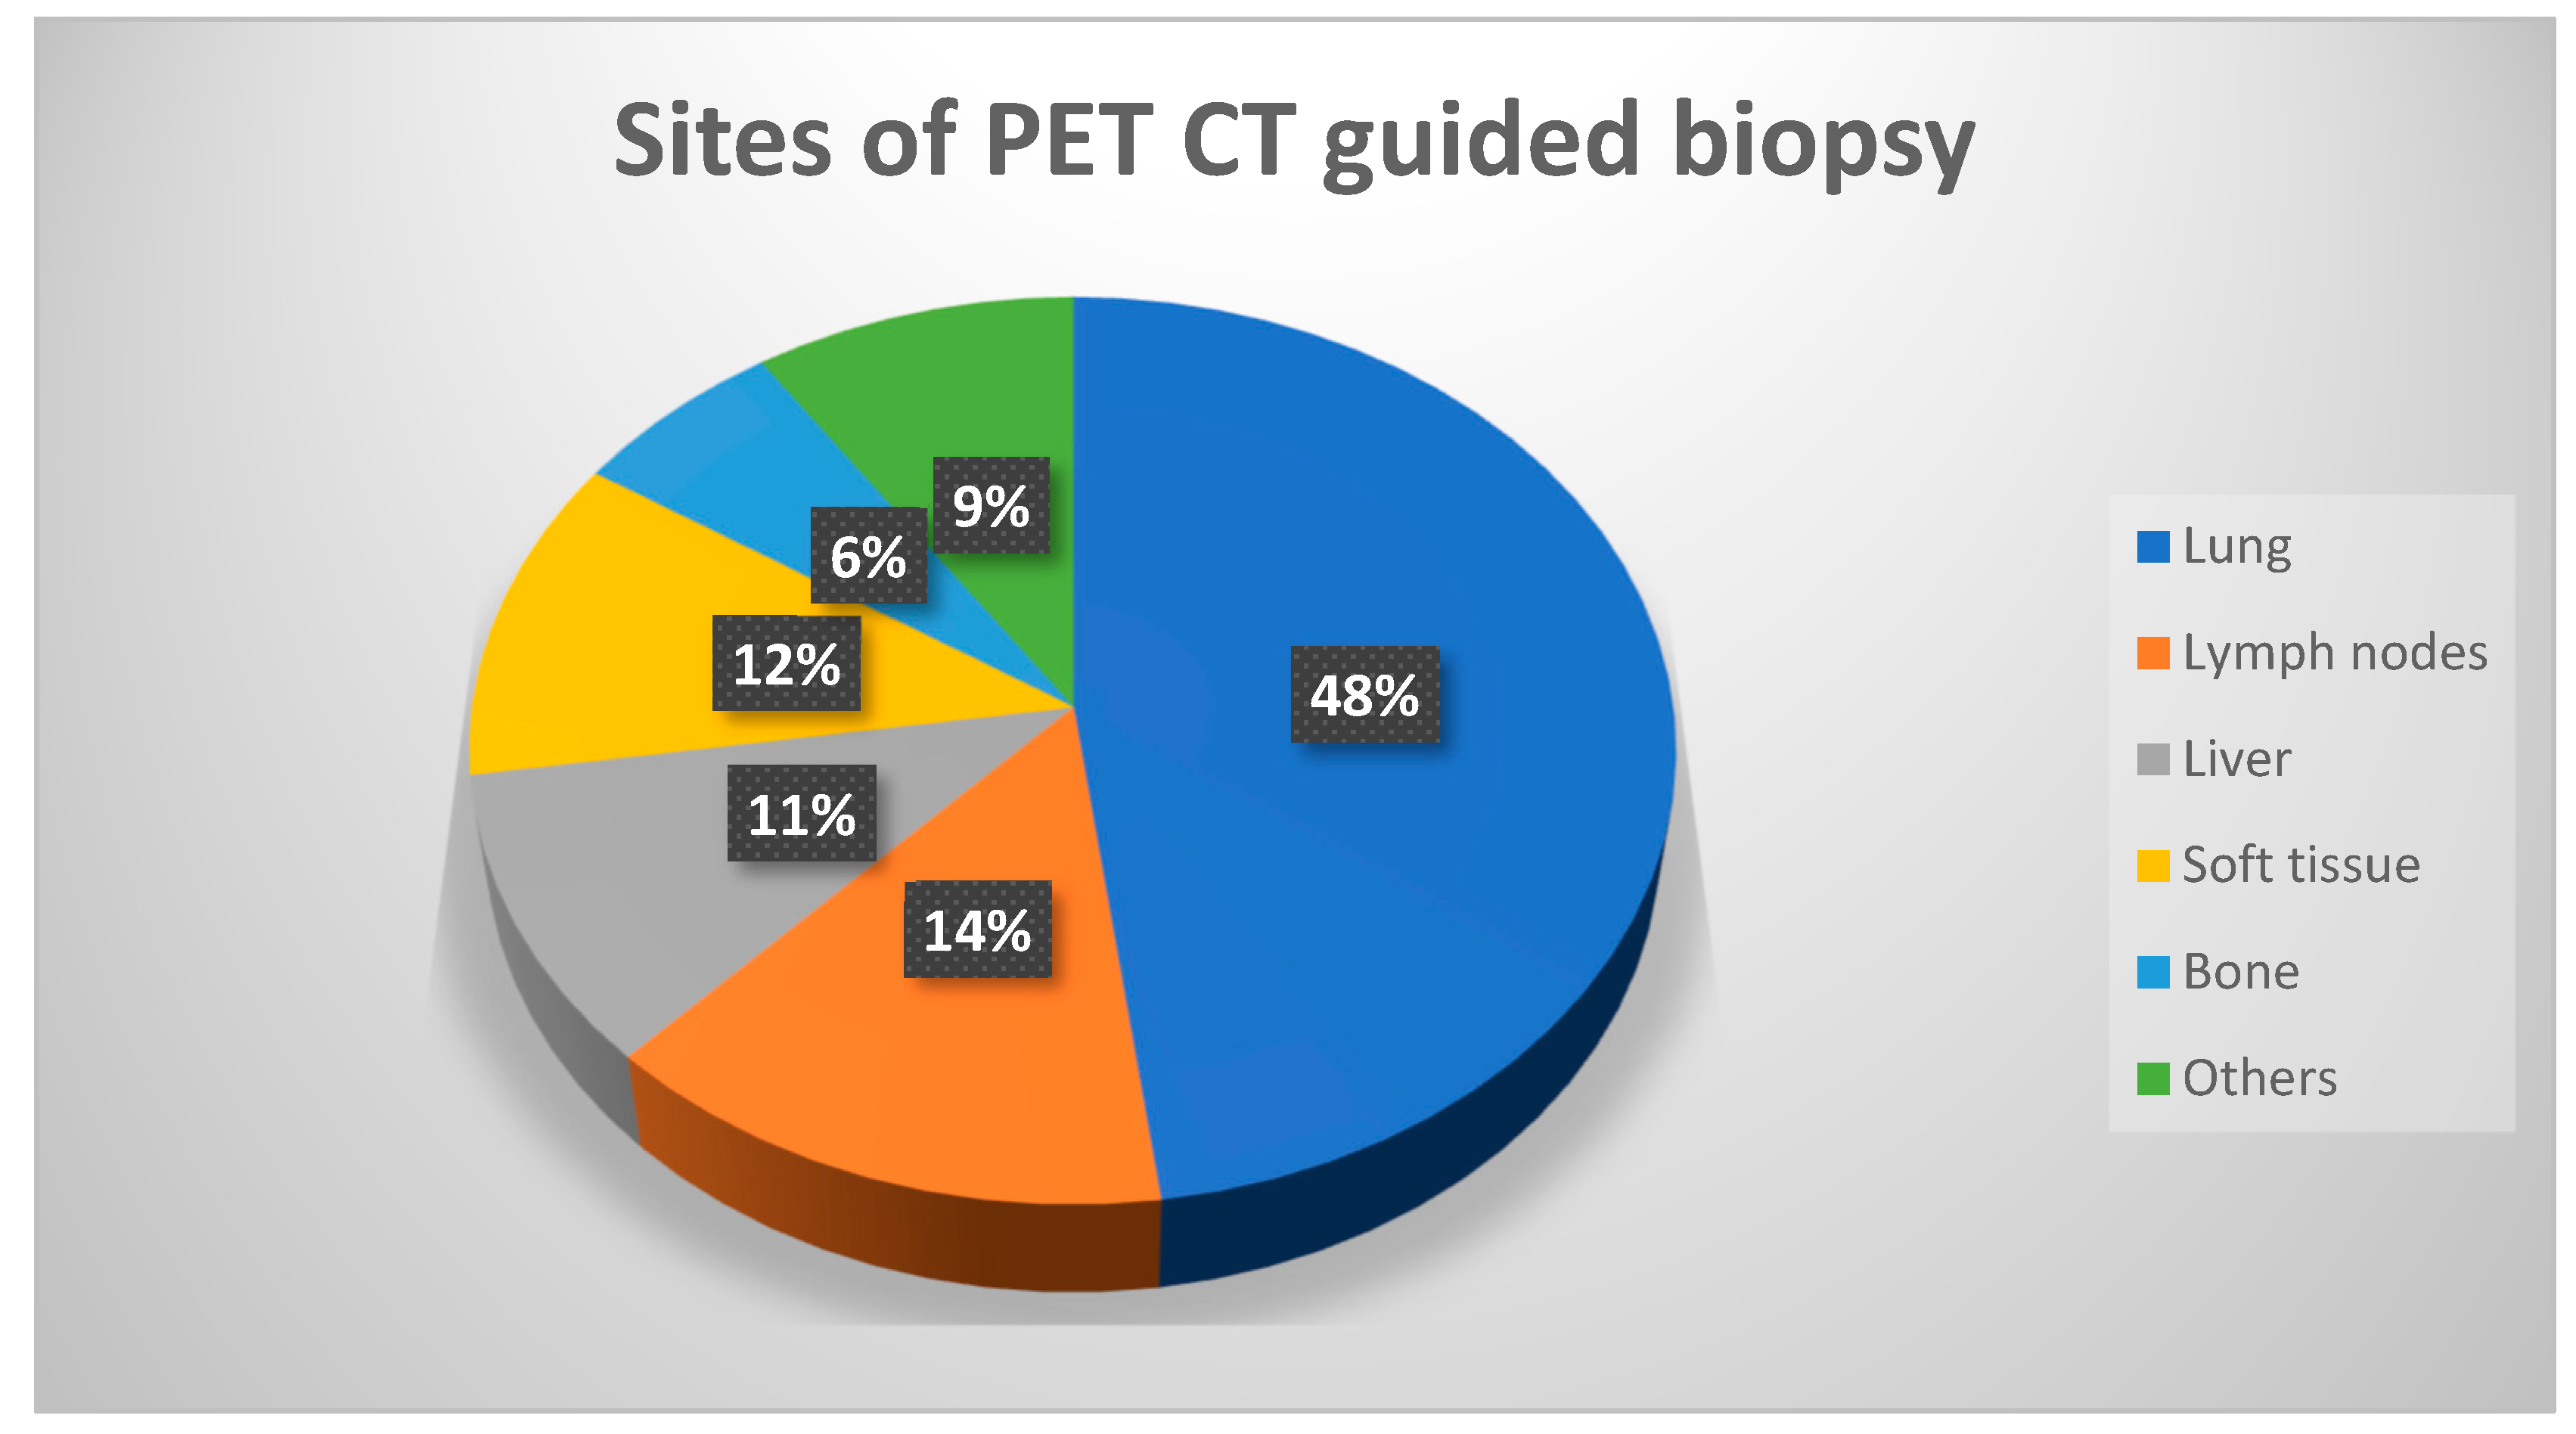

Table 1 provides a complete summary of patients’ demographics, clinical features, and pathological findings. The average age of the patients was 52.5 (in a range of 7 to 80) years. Among the samples collected during metabolic biopsies, the lung lesions comprise the biggest cohort, followed by lymph nodes and soft tissue lesions, respectively; details of sites of biopsy are provided in

Figure 1. Except for two individuals, sufficient samples were acquired from all patients. These two individuals received positive diagnoses of cancer but inadequate material for further IHC characterisation. Histopathological study reveals that 162 (85%) of the lesions were malignant and 28 (15%) were benign (